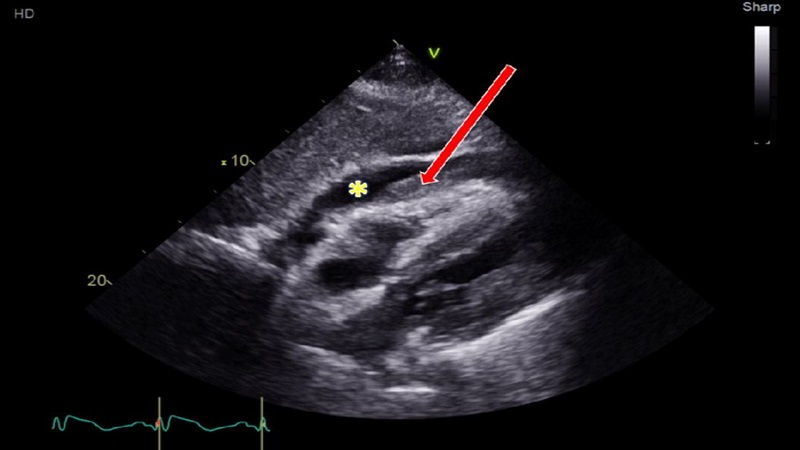

Chèn ép tim cấp là tình trạng một lượng lớn máu hoặc dịch cơ thể tràn vào màng ngoài tim, gây áp lực lên tim và khiến cơ quan này bị cản trở hoạt động hoặc mất dần chức năng. Vấn đề sức khỏe nói trên diễn tiến rất nhanh, chúng gây ra những hệ quả tức thời như:

Khi chẩn đoán bệnh lý này, bác sĩ thường kết hợp đồng thời 3 phương pháp: